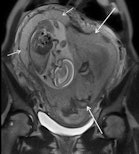

- Placental abruption: MRI should be considered after negative ultrasound findings when there is high clinical suspicion and when a firm diagnosis of abruption would change clinical management.

- Placenta adhesive disorders: Ultrasound for patients with clinical risk factors; proceed to MRI for equivocal cases, especially in patients with posterior placenta and previous myomectomy.

- Uterine rupture: MRI to diagnose antepartum uterine rupture in patients with indeterminate ultrasound evidence, showing the tear itself, and other uterine wall defects, including uterine dehiscence.